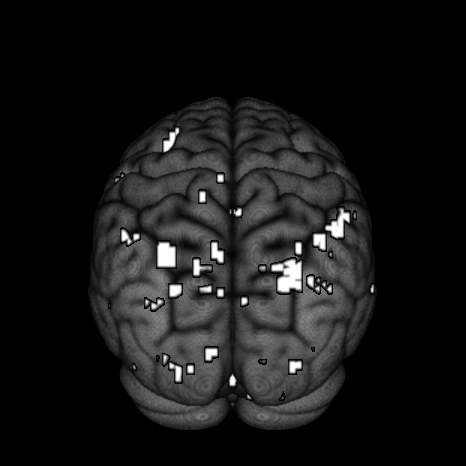

Finally, we look at the effect of fame using thresholded PPMs. The activation threshold is set to of the global mean value, and the probability threshold is set to . Figure 9 shows the activation regions projected onto the pial surface. We can see that there is a match in terms of a majority of activation regions inferred from SVARO and PMCMC. A closer look reveals that PMCMC tends to make more scattered predictions across the posterior regions of the brain. The number of activation regions from PVB are far greater than the number obtained from the other two approaches, and are more widely dispersed across the brain. From our simulation study results, we suspect that these scattered activated regions are likely false positives.